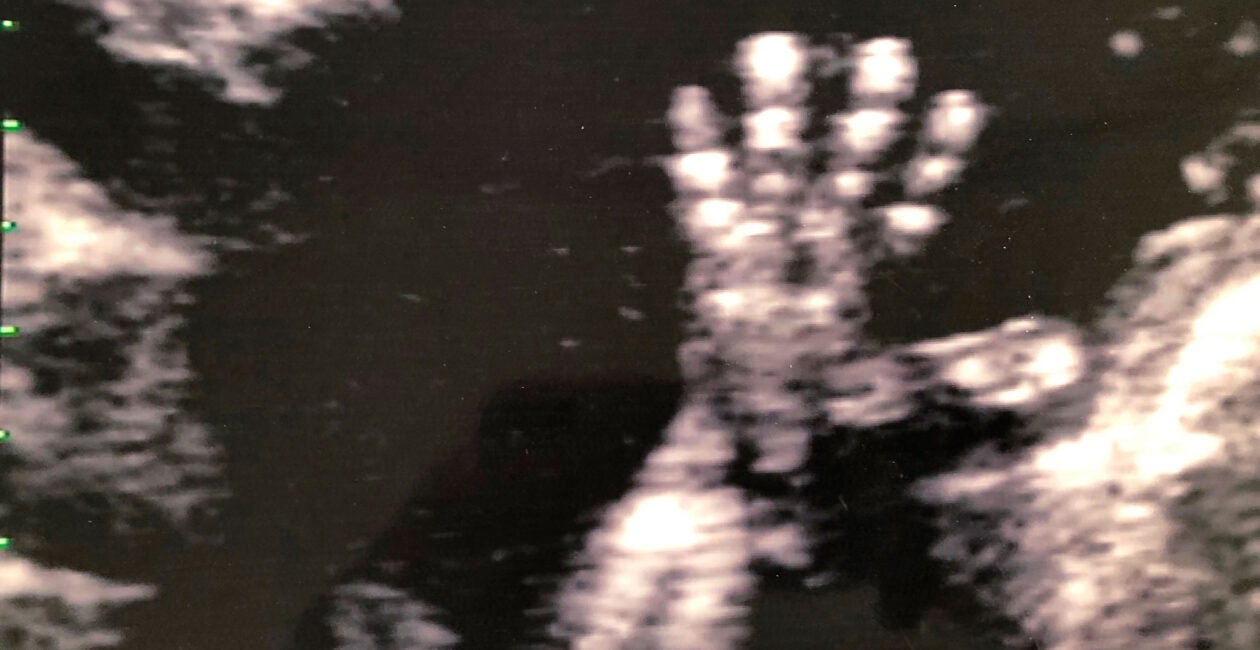

If we are to be pro-science, it is worthwhile to note that every major medical textbook on this subject makes clear that the young one developing in the womb is a living being of the species homo sapiens.

The Scriptures teach in Psalms 139:13-14: “For you created my inmost being; you knit me together in my mother’s womb. I praise you because I am fearfully and wonderfully made. Your works are wonderful. I know that full well.” Likewise, it also makes plain from Hebrew law that an unborn child should be treated as a human being (Exodus 21:22-25).